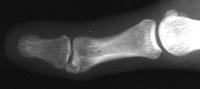

Case 3. 21 year old woman with pain developing in a congenitally angulated thumb.

Radiographs show a juxtaarticular ossification with  subchondral cyst formation of the bone interface with the lateral phalangeal head and lateral angulation of the proximal phalanx articular surface.